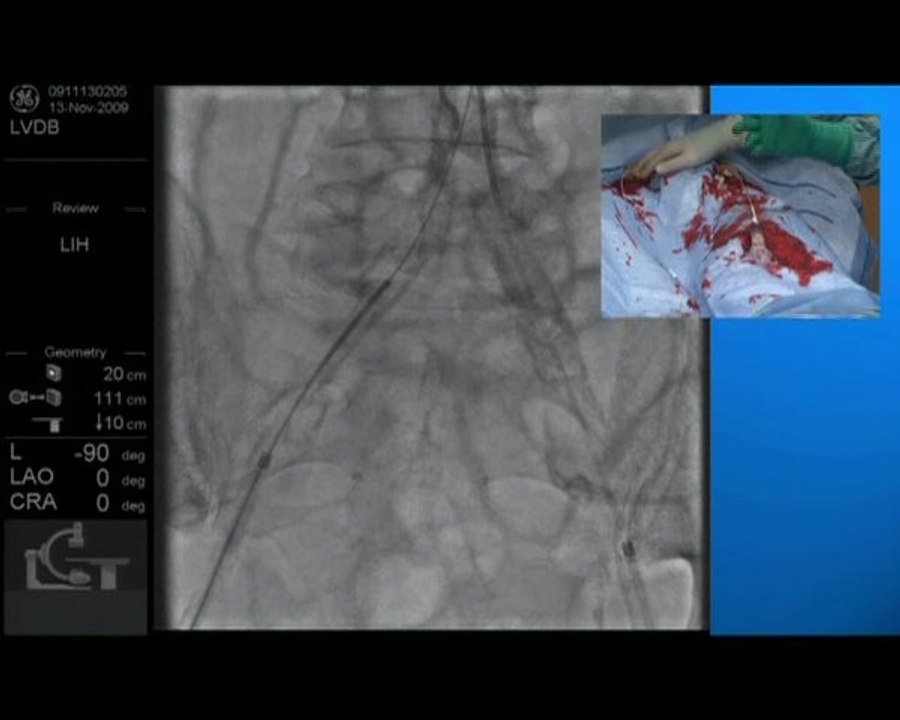

06 right coronary cto recanalization by antegrade approach incathlab.com